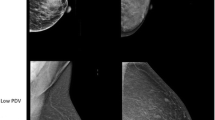

While mammography remains the cornerstone of early breast cancer detection [8], it also provides a readily accessible method to assess the distribution of fatty and dense, or fibroglandular (stromal and epithelial), tissues in the breast. In x-ray imaging, fatty tissue appears radiographically lucent, or darker, and dense tissue is radio-opaque, or brighter. Mammographic percent density (PD), a measure of the relative amount of fibroglandular tissue within the breast, has been shown to be related to screening sensitivity and specificity and has also been established as a strong independent risk factor for breast cancer [9–12]. Studies have repeatedly shown significant associations with breast cancer risk for both qualitative and quantitative breast density measures and a potential to improve cancer risk assessment models [13, 14]. Recent legislation in several US states mandates notification of breast density [15], and substantial research continues to be devoted to accurate measurement of this key biomarker and to its incorporation into risk prediction models [9, 16].